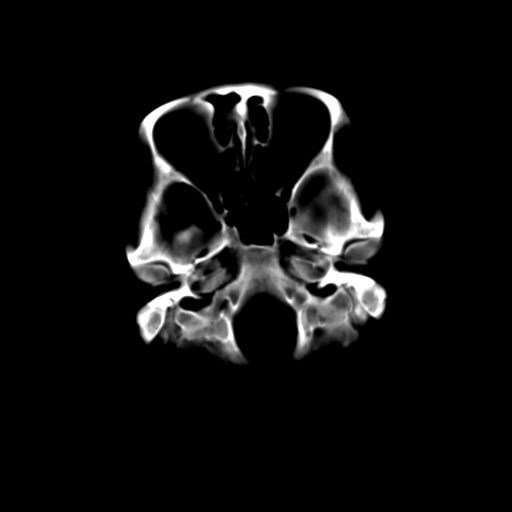

考虑枕骨血管瘤

颅内未见明显异常,枕骨松质骨瘤可能性大。颅骨板障起源骨瘤较常见,骨血管瘤有垂直骨针及粗大钙化,嗜酸性肉芽肿软组织有改变,典型者可见“纽扣状”死骨,年龄通常较小。

左枕骨松质骨不均匀低密度灶,边缘清楚,考虑良性松质骨性骨瘤可能性大。

以下是引用sunbin在2010-1-6 14:39:00的发言:[br]左枕骨松质骨不均匀低密度灶,边缘清楚,考虑良性松质骨性骨瘤可能性大。

不排除左枕骨嗜酸性肉芽肿可能。